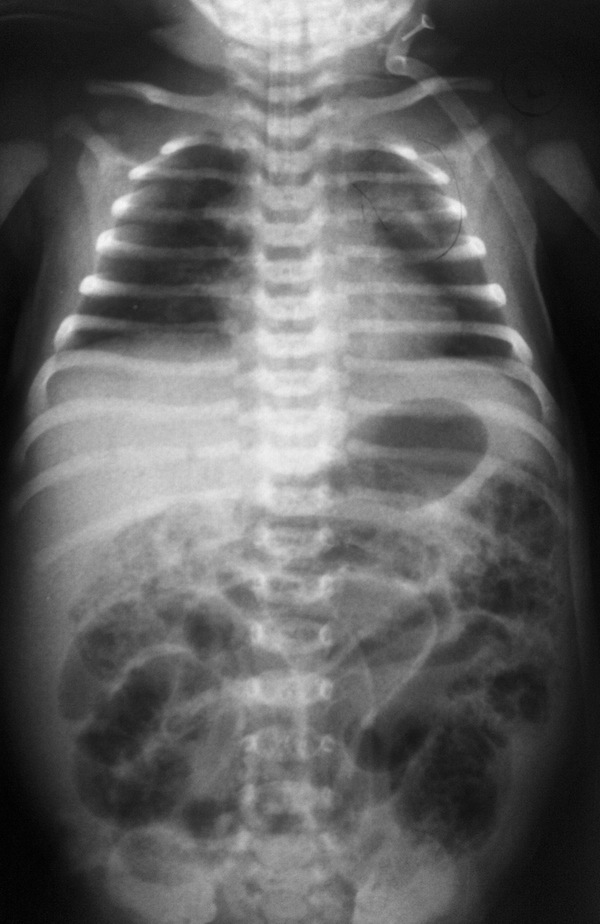

Среди приведенных диагностических тестов наиболее постоянными и информативными являются изменения в гемограмме (лейкоцитоз / лейкопения, сдвиг лейкоформулы влево, тромбоцитопения), повышение С-реактивного протеина, ацидоз, электролитный дисбаланс, интерстициальный пневматоз и газ в портальной венозной системе по данным ультразвукового и рентгенологического исследований органов брюшной полости.